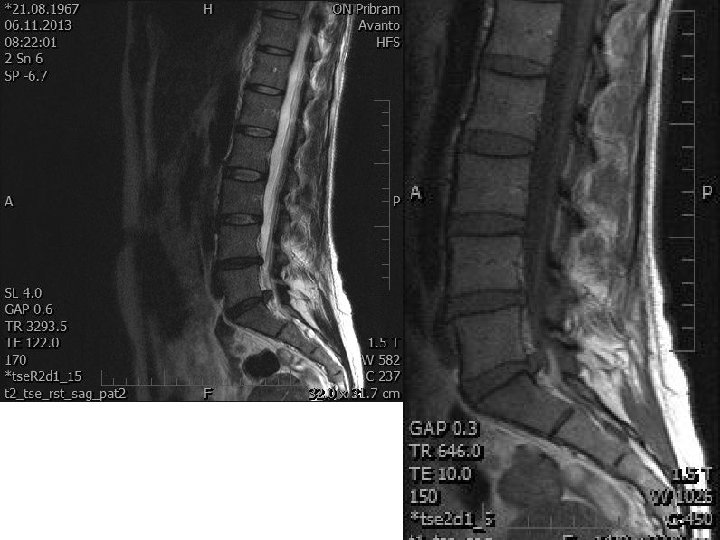

The MRI image n 11/2013 of the lumbar spine at the area L 4/5 there is asymmetric protrusion medially to paramediat to the right, the size 3 mm. The region L 5/S 1 there is disc herniation in the foraminal to preforaminal the right size. 8 x 12 x 9 mm, fill the right lateral recesus which pushes the outgoing root S 1 on the right. Focal herniation (extrusion) of the disc L 5/S 1 preforaminal with the pressure to the leaving root S 1 on the right.